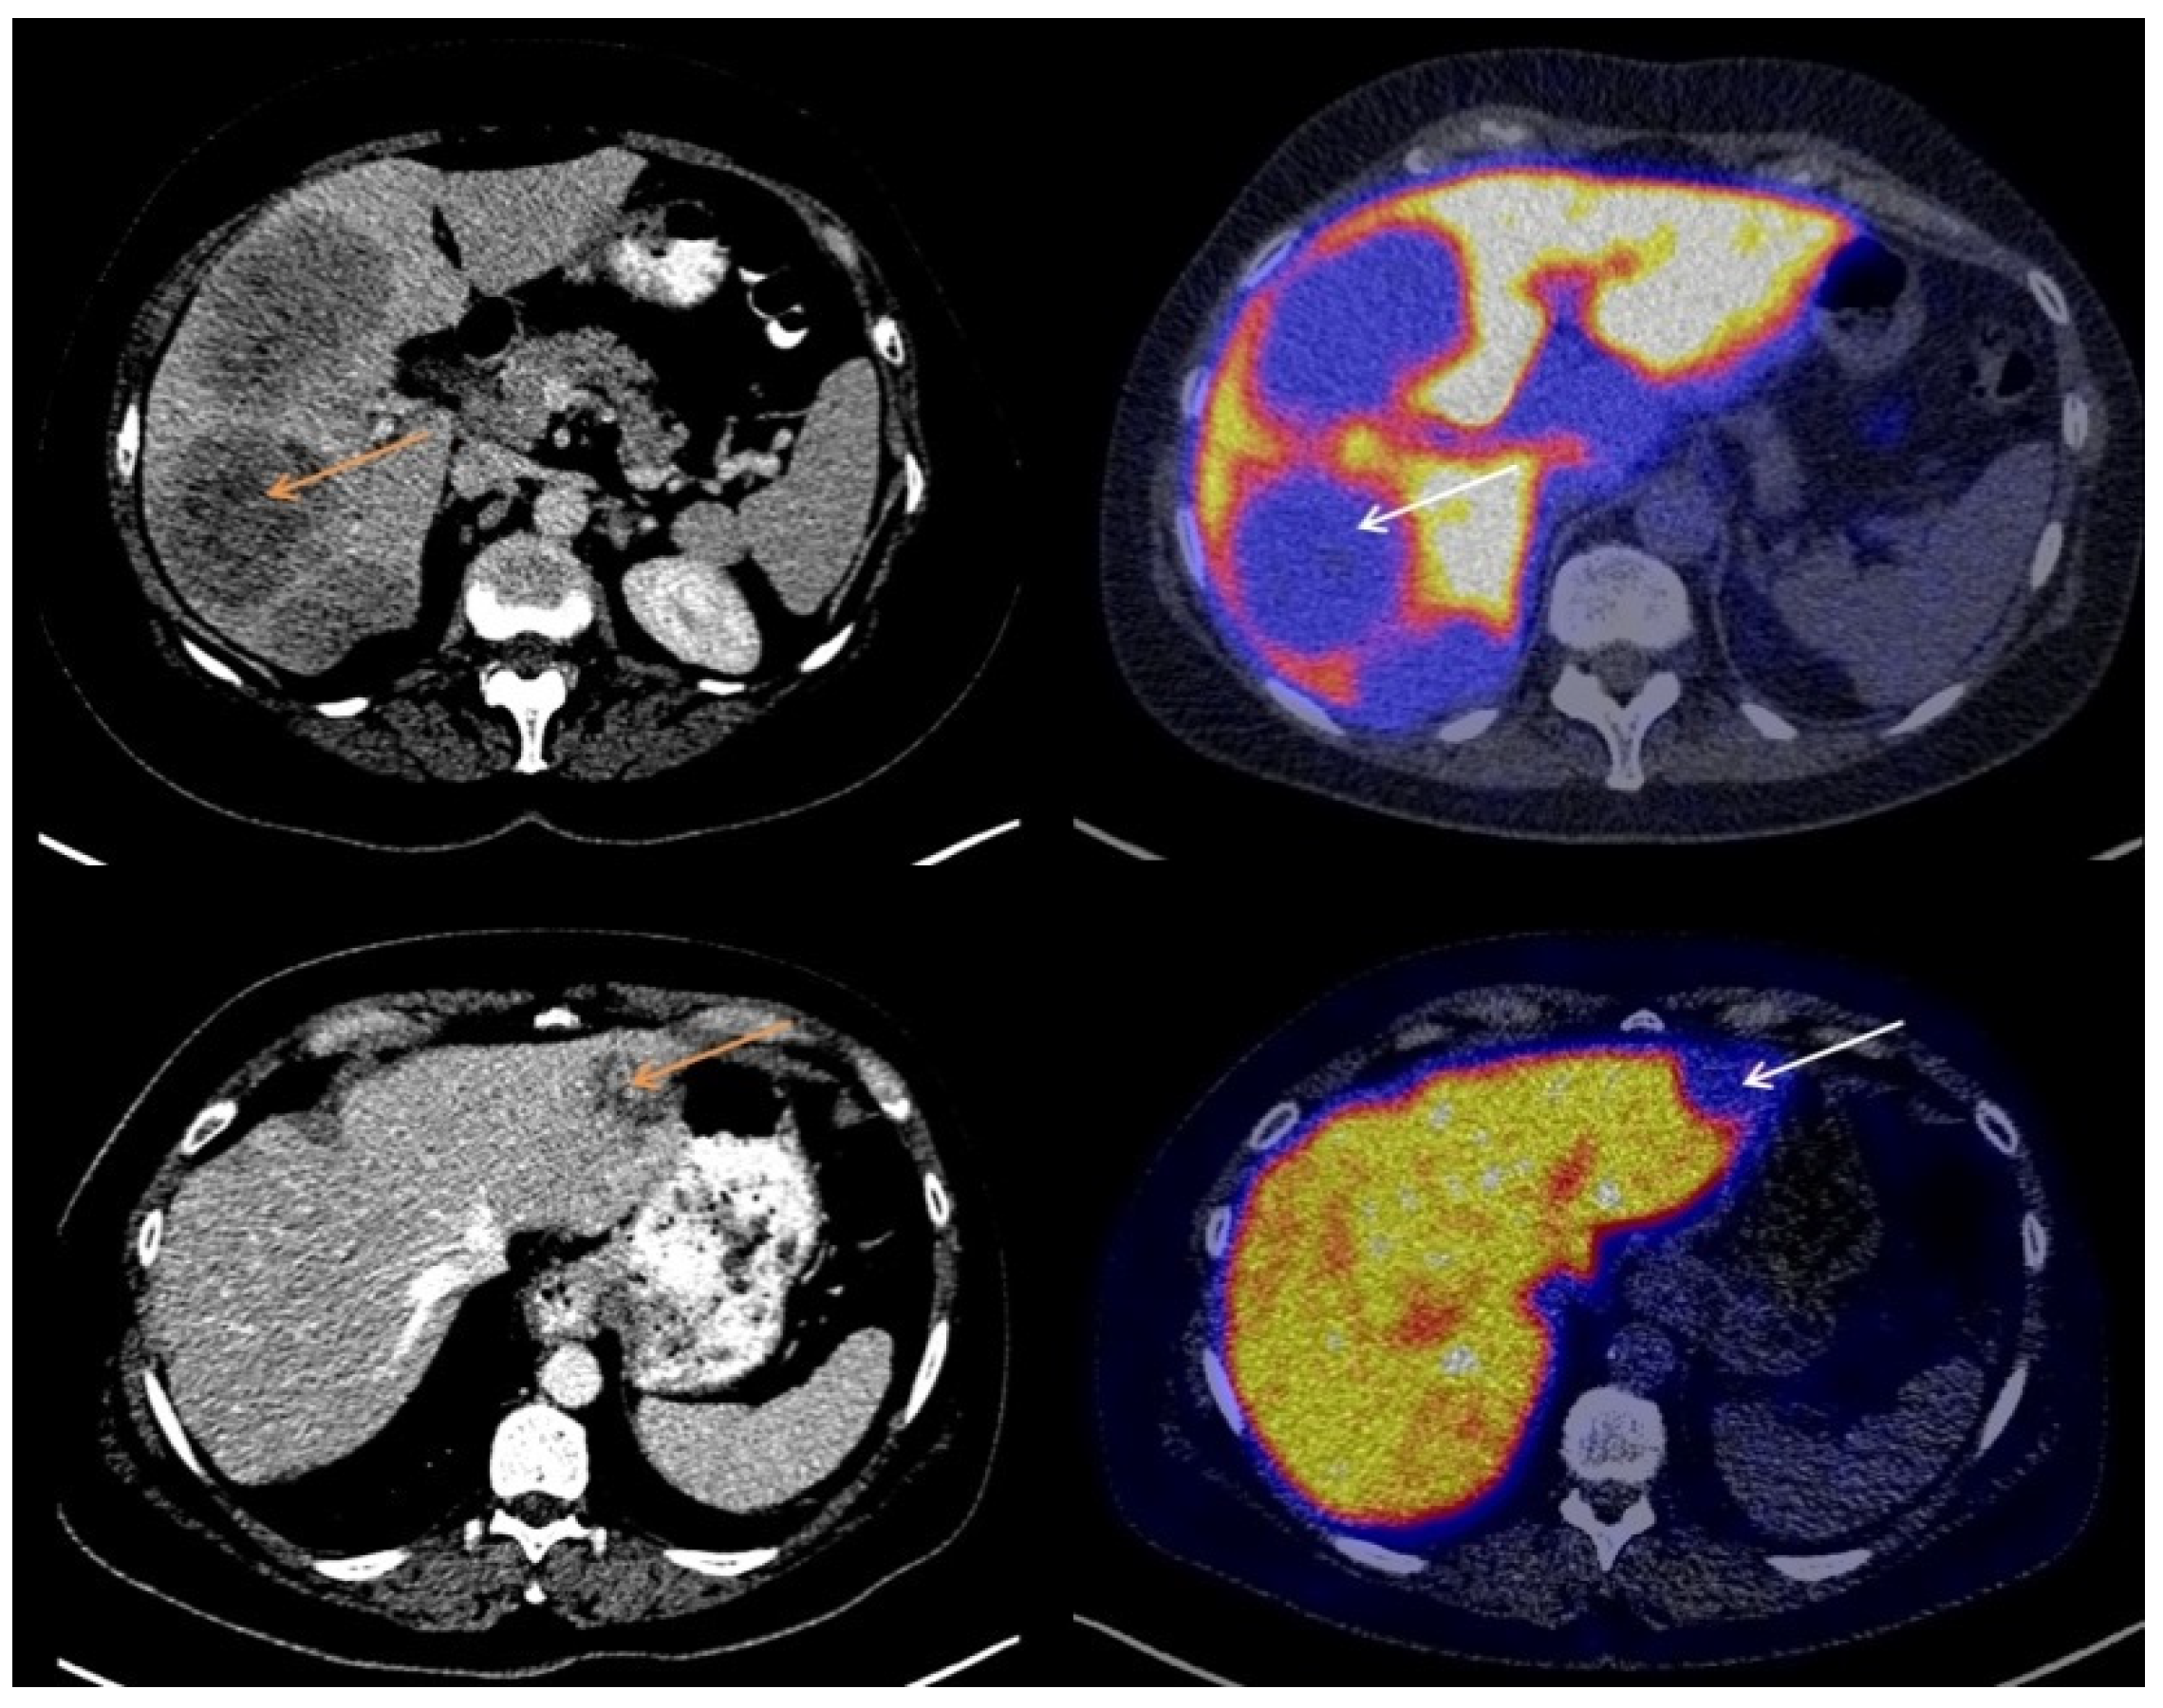

3.2. Visual Assessment of [18F]-FES Uptake

3.3. Quantitative Evaluation of [18F]-FES Uptake

3.4. The Effect of ROI Size